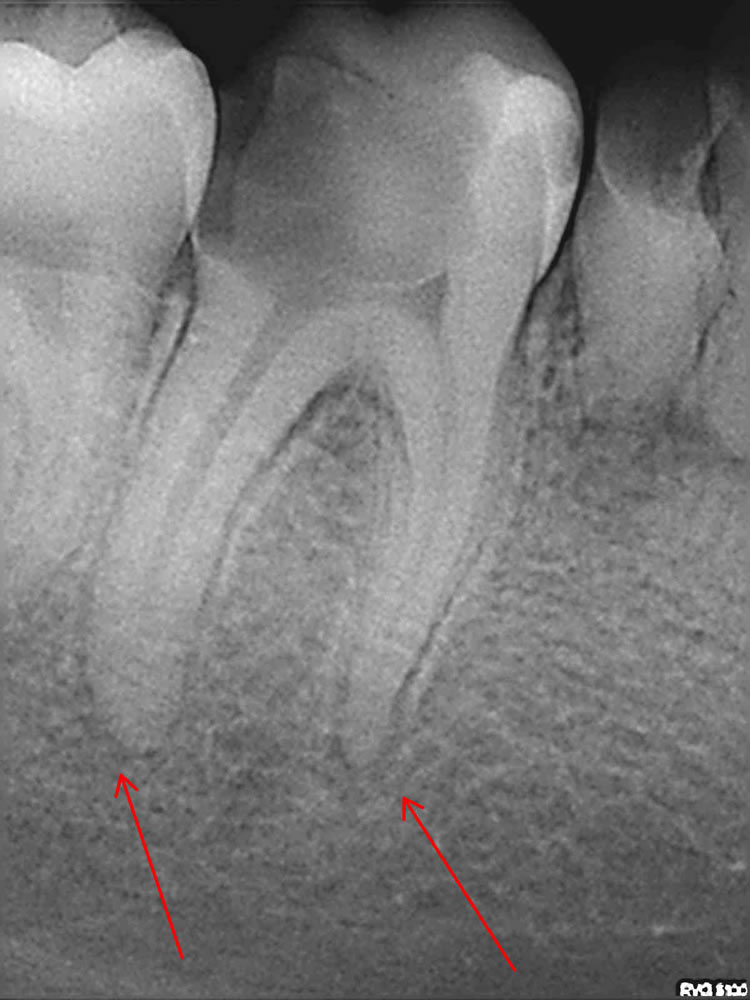

Sam postupak endodontskog liječenja započinje postavljanjem dijagnoze kliničkim pregledom i rtg snimkom. Rtg snimanje je obavezno prije samog liječenja jer se njime vide uzroci bolesti, postojanje eventualnog procesa u kosti te ono što je jako važno za samo liječenje, broj korjenova i kanala, zakrivljenost i druge njihove morfološke varijacije. Time se doktoru dentalne medicine omogućuje orijentacija u prostoru korijenskih kanala. Na osnovu rtg snimke doktor dentalne medicine može ocijeniti postoji li uopće mogućnost liječenja te predvidjeti moguće poteškoće u postupku.

Nakon završenog liječenja, kvaliteta punjenja se provjerava rtg snimkom čime se procjenjuje dužina i kompaktnost punjenja. Tek ako je rentgenogram potvrdio dovoljno kvalitetno punjenje, zub se rekonstruira bilo ispunom ( "plombom" ) ili protetski ( nadogradnja i krunica ).

U slučaju postojanja periapikalnog procesa ( granuloma ) zub se ponovno kontrolira nakon šest mjeseci, nakon godinu, odnosno dvije godine. Uspješnost liječenja se procjenjuje na temelju cijeljenja granuloma koji nestaje na čijem mjestu se stvara nova kost. To dovodi do odgovora na pitanje koje se često postavlja doktoru dentalne medicine:"Je li moguće liječiti granulom liječeći zub?" Odgovor je: "Svakako da, jer su uzrok granulomu iritansi iz korijenskog kanala. Kad se oni uklone, organizam sam zacijeli oboljelo tkivo".